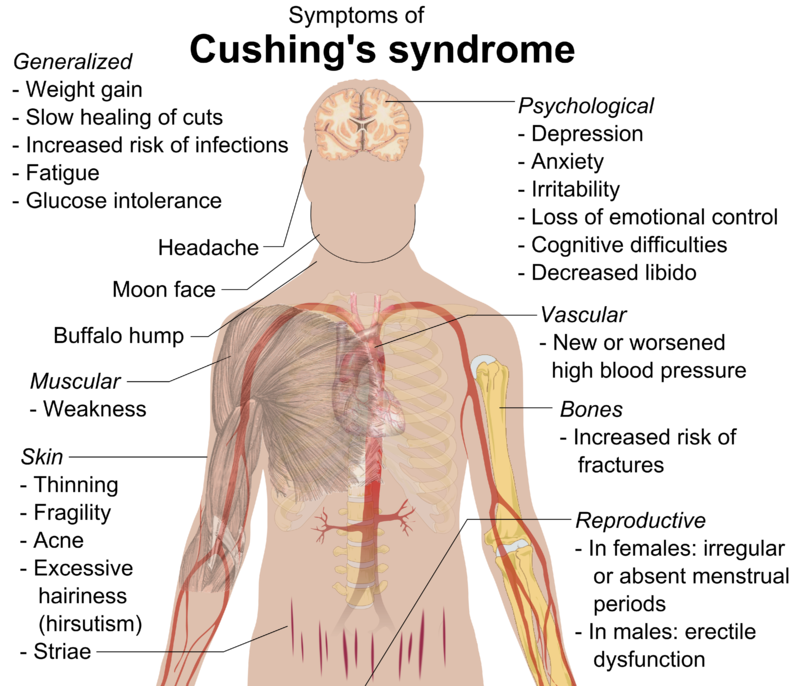

Cushing Syndrome (Hypercortisolism)

When there is too much cortisol in the body, Cushing’s syndrome develops.

The stress hormone or cortisol, is essential for controlling blood sugar and converting food into energy.

There are several clinical features of Cushing syndrome includes:

- Muscle weakness

- Thin extremities when cortisol breaks down muscle for gluconeogenesis

- Moon facies

- Buffalo hump

- Truncal obesity with high insulin due to high glucose increased storage of fat

- Hypertension

- Osteoporosis

- Immunosuppression

- Abdominal striae due to impaired collagen synthesis with skin thinning